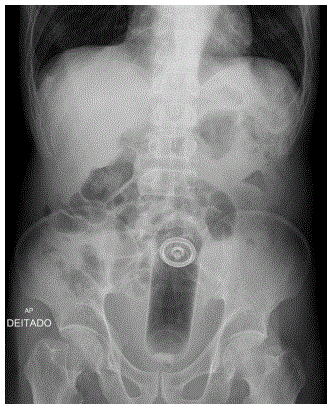

Paciente sexo masculino, 42 anos, procura serviço de emergência queixando-se de dificuldade para evacuar e eliminar gases há 2 dias, acompanhado de cólicas abdominais. Refere ter eliminado muco com laivos de sangue. Sem antecedentes mórbidos.

Ao exame físico: PA: 140 X 80 mmHg; Pulso: 90 bpm (rítmico e cheio).

FR: 14 ipm; Tax: 36,8º C.

Bom estado geral, corado, desidratado+, afebril e anictérico.

Tórax sem anormalidades ao exame.

Abdome: distendido+, flácido, doloroso à palpação com massa palpável no hipogástrio, descompressão brusca negativa. Ruídos hidroaéreos presentes.

Conduta:

• Hidratação com solução cristaloide

• Analgesia

• Solicitado exame de imagem (RX abdome) mostrado ao lado.

Qual é a abordagem mais indicada a ser realizada a seguir, com base nos dados clínicos e no exame de imagem?